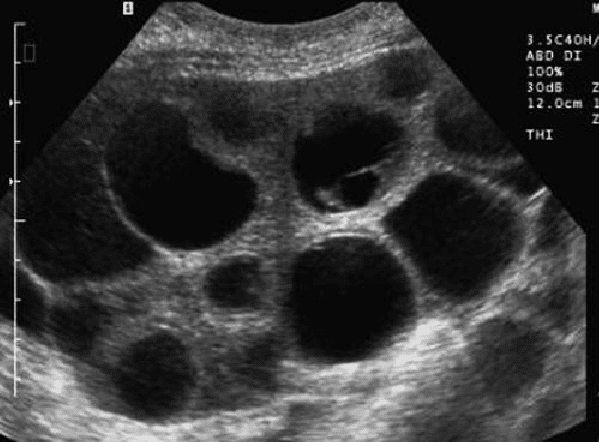

Ultrasound image of severe OHSS (Source)

Ultrasound scans and blood tests are used to monitor the number and size of follicles, as well as hormone levels. There is no set number of follicles that puts you at risk of developing OHSS, as the risk varies depending on other factors such as age, body weight, and response to medications. However, as a general guideline, having more than 20 follicles on an ultrasound scan is considered a high risk for OHSS. If you are deemed to be at high risk of developing OHSS, your doctor may adjust your medication dosages or cancel the cycle to prevent OHSS from developing.